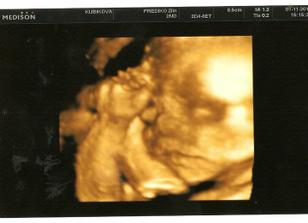

1.11. 3D ultrazvuk 🙂